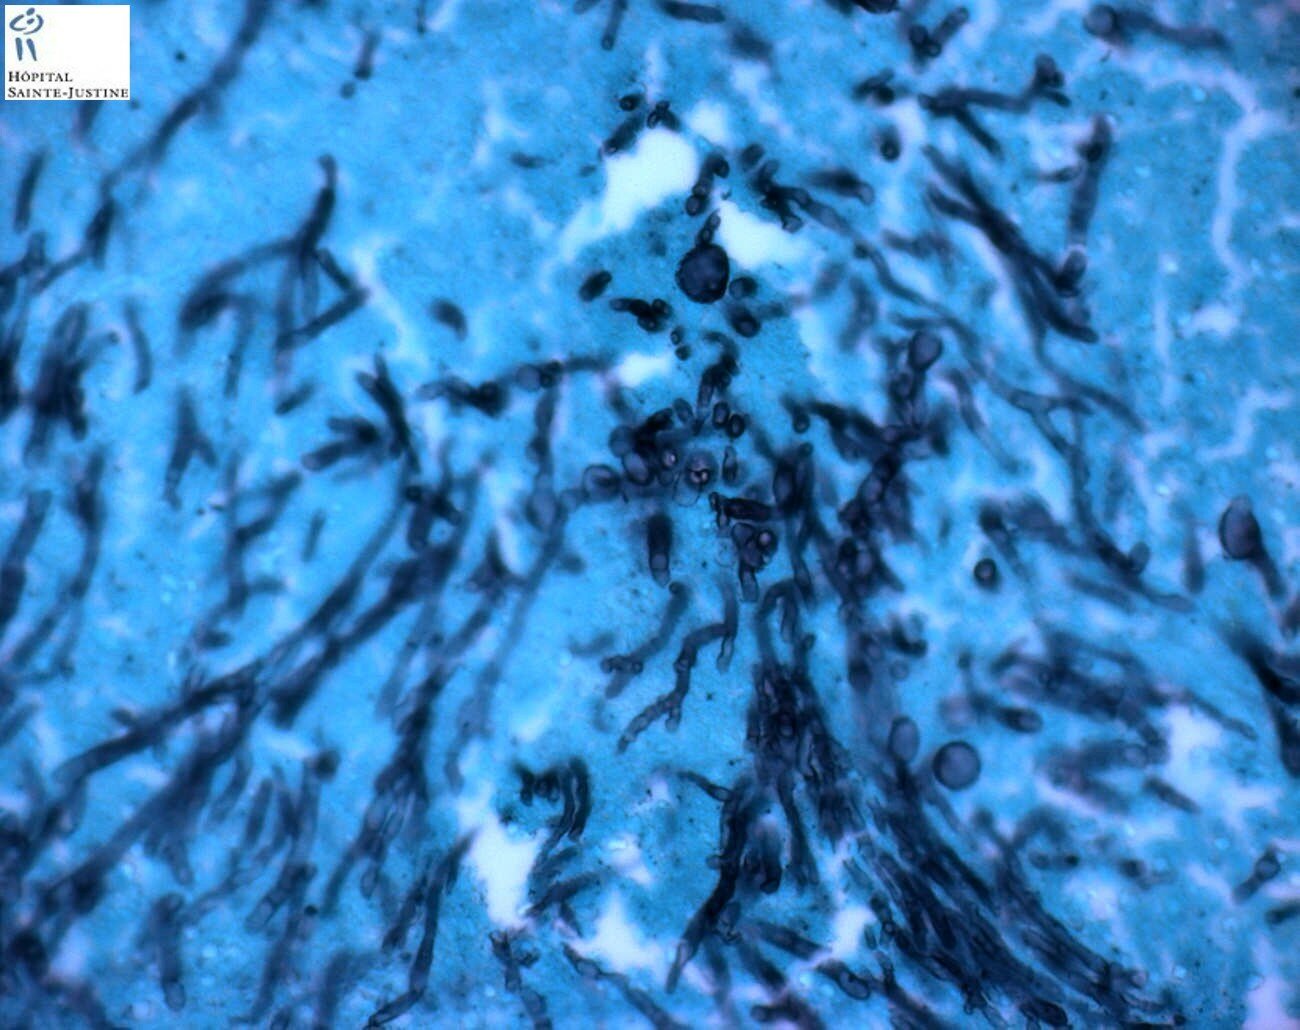

invasive pulmonary aspergillosis

Invasive pulmonary aspergillosis Invasive pulmonary aspergillosis Invasive pulmonary aspergillosis invasive pulmonary aspergillosis invasive pulmonary aspergillosis invasive pulmonary aspergillosis invasive pulmonary aspergillosis invasive pulmonary aspergillosis invasive pulmonary aspergillosis invasive pulmonary aspergillosis invasive pulmonary aspergillosis invasive pulmonary aspergillosis invasive pulmonary aspergillosis invasive pulmonary aspergillosis Invasive pulmonary aspergillosis